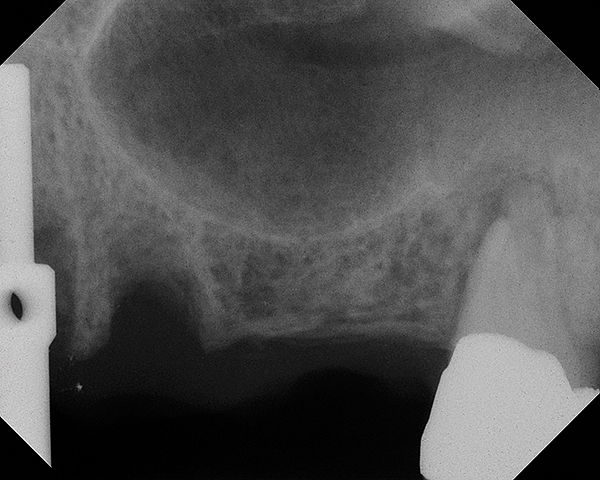

A 74-year-old man presented with only about 2 mm to 3 mm of native bone below the sinus in the No. 14 position (Figure 13). The composite graft used was an approximately 50:50 mixture of DFDBA (Bio-Oss®, Geistlich Biomaterials, www.bio-oss.com) with the addition of about 40% calcium sulfate by volume (Figure 14). The implant placed (Figure 15) was a 10-mm long, rough-surfaced, platform-shifting implant (tapered 4.2 mm to 2.8 mm), and the sinus was raised about 8 mm. The postoperative radiograph taken at 4 months (Figure 16) showed some shrinkage of the graft, but no demarcation of the old sinus floor in the area.

Fig 13. Case 1. Preoperative radiograph showing a ridge height of about 2 mm to 3 mm in the No. 14 position.

Figure 13

Fig 14. Radiograph of sinus composite bone augmentation in the No. 14 position.

Figure 14

Fig 15. Radiograph of implant No. 14 with sinus augmentation, day of placement. The floor of the sinus has been raised about 7 mm to 8 mm.

Figure 15

Fig 16. 4-month radiograph with the abutment No. 14 in place. Note the ill-defined old sinus floor.

figure 16